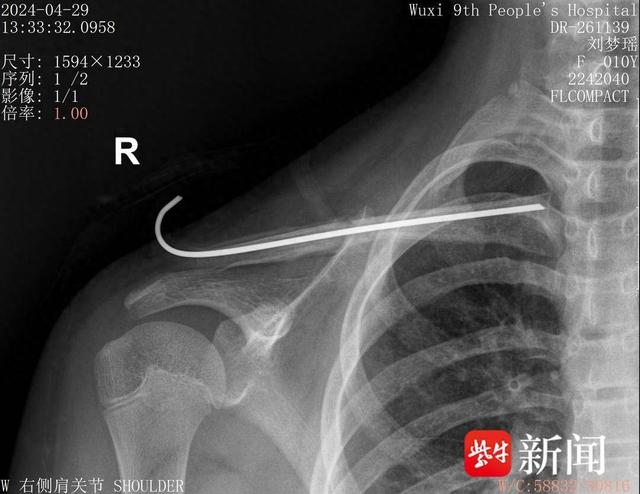

锁骨骨折,机器人规划路线"按图索骥"精准手术

图片尺寸640x494